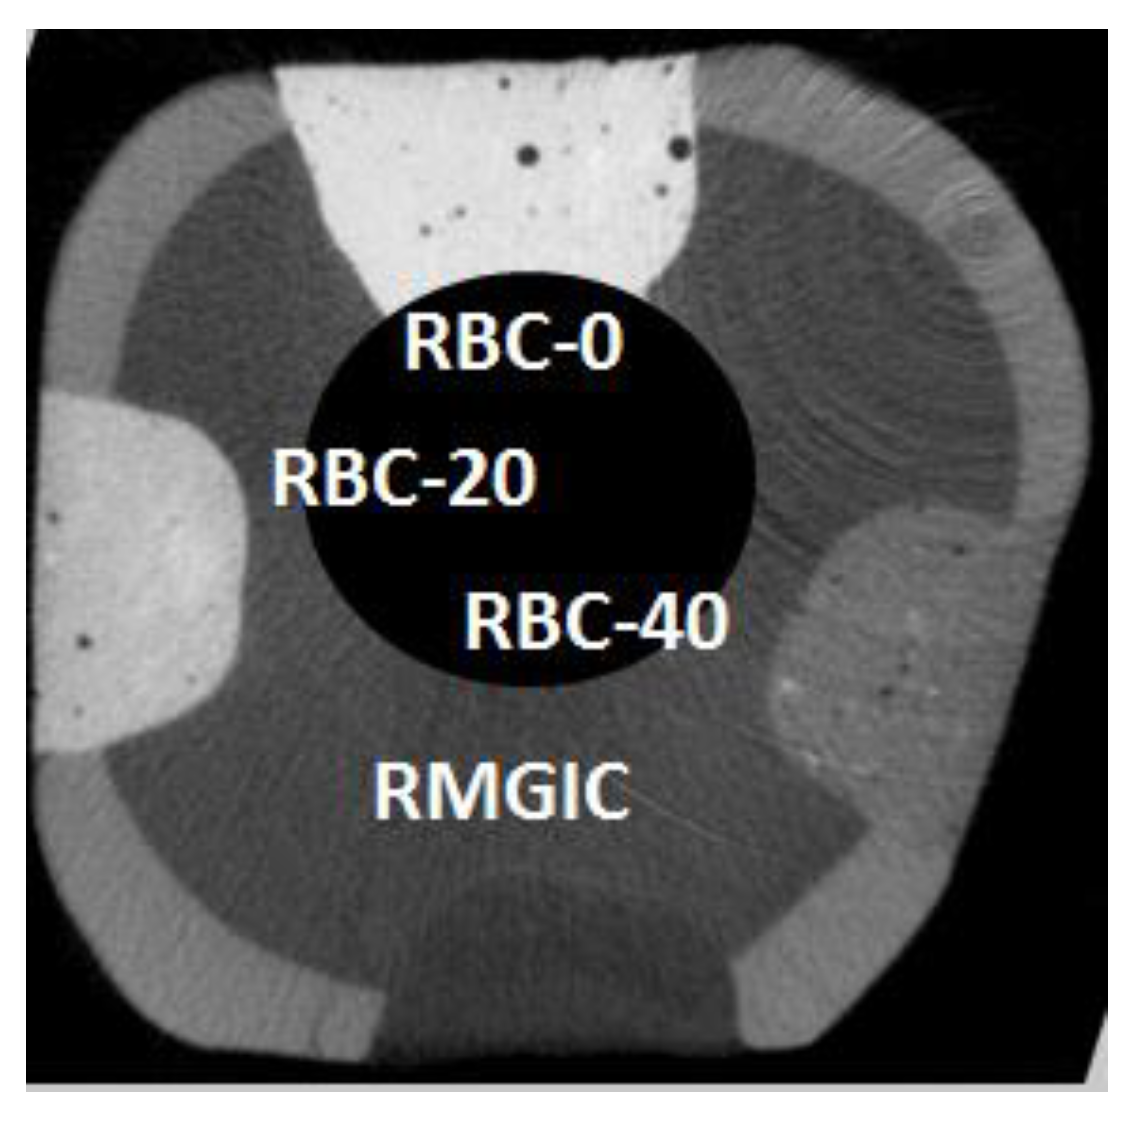

2.11. Microtomography

3.5. Secondary Caries Models

| Material | Margin | Margin + 1.0 mm |

|---|---|---|

| RBC-0 | 214.5 (44.9) a | 163.4 (29.8) a |

| RBC-20 | 156.5 (42.8) a | 157.9 (58.1) a |

| RBC-40 | 80.8 (33.6) b | 144.8 (34.6) a |

| RMGIC | 84.4 (47.6) b | 148.8 (41.6) a |